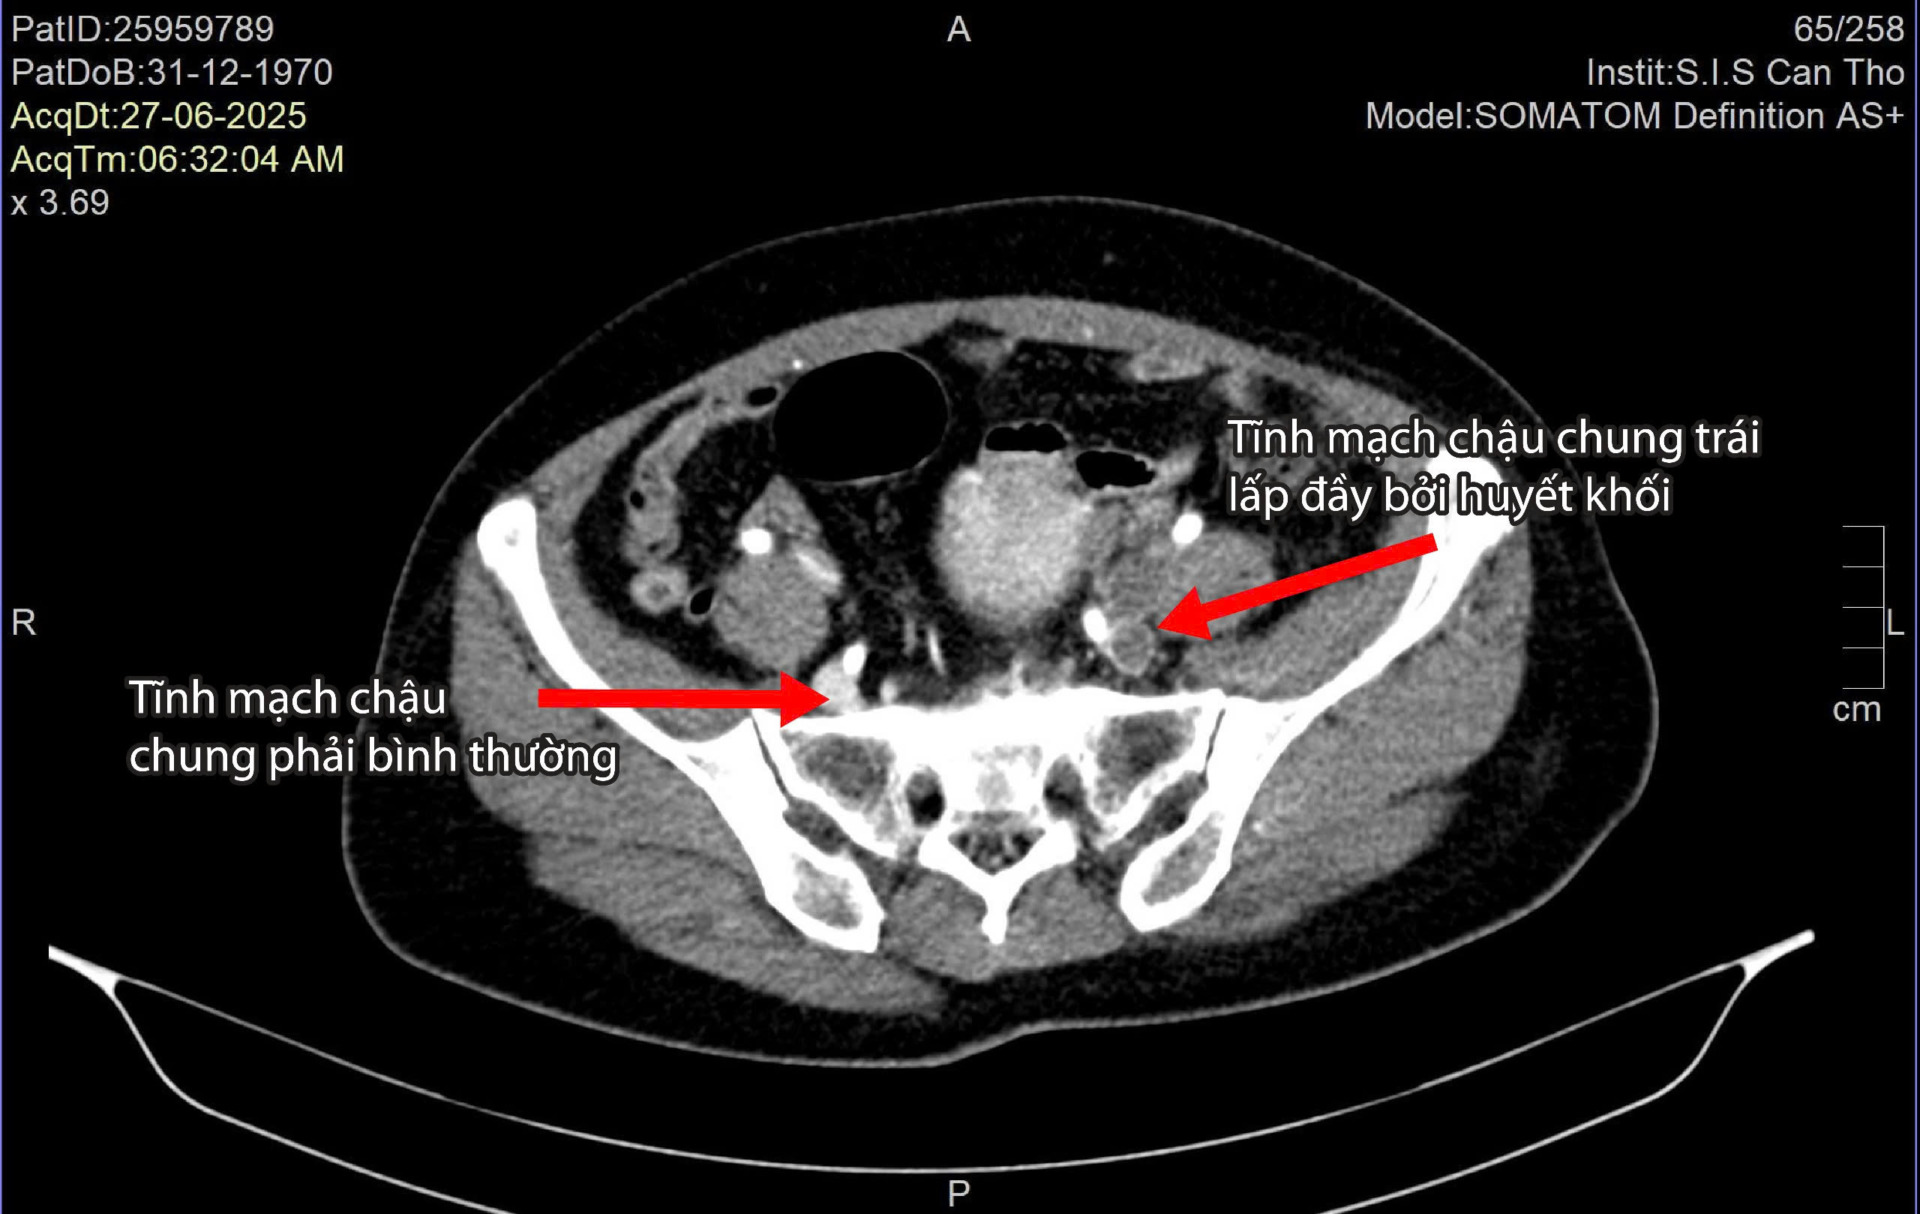

Một cụ ông 65 tuổi (ở Đồng Tháp) bị đau dữ dội vùng thắt lưng và hai chân đến mức không thể đi lại, đứng trước nguy cơ đoạn chi. Gia đình đã đưa ông đi khám nhiều nơi nhưng chưa an tâm, sau cùng chuyển đến Bệnh viện Đa khoa Quốc tế S.I.S Cần Thơ, nơi ông được điều trị và phẫu thuật thành công, giữ lại được đôi chân.

Nhập viện trong tình trạng chân trái tím tái, sưng phù một cách bất thường, không thể tự di chuyển, nữ bệnh nhân 57 tuổi suýt phải đoạn chi. Rất may, bà được bệnh viện Đa khoa Quốc tế S.I.S Cần Thơ can thiệp tái thông tĩnh mạch chi thành công.